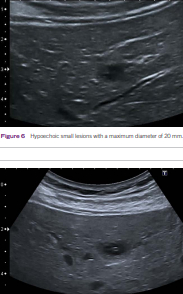

hepatic candidiasis

(most commonly) pneumocystis carinii (associated with hepatic granuloma)

hepatic granulomas (associated with pneumocystis carinii)